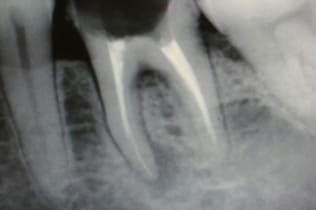

根管治療は無菌の根管を作り、緊密な根管充填が絶対条件です。歯の寿命がこれで決まると言っても過言ではありません。下の写真は根管充填不良により引き起こされた、根尖性歯周炎の状態です。左が根管治療前、右が根管充填後のレントゲン写真。

-

術前

CWCT法による根管治療の術後